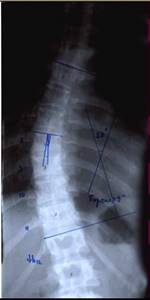

До сих пор в ортопедии принято множество методик измерения угла искривления позвоночника, и, соответственно, множество различных классификаций с разными величинами углов в градусах. Измеряется искривление так: на рентгенограмме надо провести несколько прямых линий между позвонками, а затем измерить углы между ними. В нашей стране наиболее распространена классификация, предложенная В.Д. Чаклиным. В иностранных научных источниках чаще приводится метод Дж. Кобба. Суть его заключается в следующем: на рентгеновском снимке позвоночника врач измеряет S-образное двойное искривление. В верхнем участке искривления с помощью линейки проводят две горизонтальные линии: одна над верхним позвонком, от которого идет кривизна, другая - над нижним. Если провести еще две линии, идущие перпендикулярно первым, образуется угол. Его и измеряют в градусах

Как видно, принцип измерения как у русского, так и американского профессора практически одинаковый. Разница в том, что по Чаклину, чем больше градусов, тем легче степень болезни, а по Коббу - наоборот.

Классификация выраженности сколиоза по В.Д. Чаклину (слева), по Лж. Коббу (справа) Степени тяжести сколиоза (углы искривления позвоночника, в градусах) Графический расчет на рентгенограмме: а - I степень; б - II степень; в - III степень; г - IV степень.

Глава 2.2 Четырехстепенная классификация сколиоза

Первая степень.

Клинически определяется небольшая ассиметрия частей корпуса (надплечий, лопаток), линия остистых отростков слегка искривлена. На выпуклой стороне искривления позвоночника может определяться небольшой мышечный валик. Появляются начальные признаки торсии позвонков. Рентгенологически угол искривления позвоночника до 10°.

Вторая степень.

Ассиметрия частей корпуса становится более выраженной, появляется небольшое отклонение корпуса в сторону. Мышечный валик четко определяется. Рентгенологически отмечается ясная торсия и небольшая клиновидная деформация позвонков. Угол искривления позвоночника

от 10° до 25°.

Третья степень.

Ассиметрия частей корпуса увеличивается. Грудная клетка резко деформирована: сзади на выпуклой стороне дуги искривления позвоночника - задний реберно-позвоночный горб, спереди на вогнутой стороне - менее выраженный передний реберный горб. В поясничном разделе часто усилен лордоз. На рентгенограмме - выраженная торсия и клиновидная деформация позвонков и дисков. Угол искривления позвоночника от 25° до 40°.

Четвертая степень.

Деформация позвоночника и грудной клетки становится грубой и фиксированной. Угол искривления позвоночника более 40°.